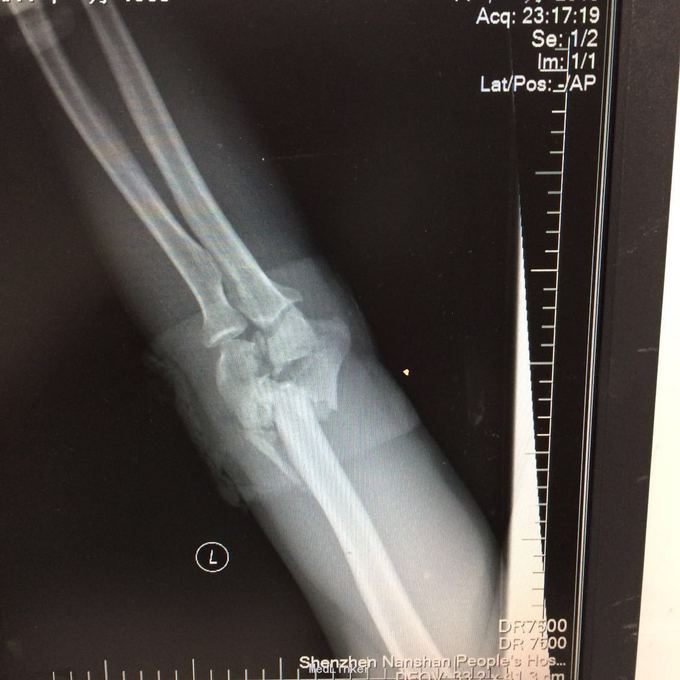

患者某某,男,49岁,因“高处坠落致全身多处疼痛、肿胀、流血2小时 1、男性壮年患者。 2、缘患者于2小时前因高处坠落致左肘、左手、右手、头面部、左胸,左足等多处受伤,即觉左肘部疼痛、活动困难、流血;左手、头面部伤口疼痛、流血;右手、左胸,左足部等处疼痛、肿胀。由家属、同事送往我院就诊,经行X线检查示:左肱骨远端粉碎性骨折,左肘关节半脱位;左手第4、5掌骨远端骨折;右手第1远节指骨基底部、第3、4远节指骨骨折,第5中节、远节指骨骨折;左跟骨粉碎性骨折。CT示:鼻中隔骨折;右侧第3--7肋骨折。急诊科予清创包扎止血,为作进一步诊治而收入院。患者受伤以来,患者精神好,无呼吸困难,无恶心、呕吐,无头晕,无面色苍白,无双下肢麻木、无力,无大小便失禁。 3、查体:T36.8 ℃ P 76次/分 R20 次/分 BP104/67mmHg。神清合作、应答切题、全身皮肤粘膜无黄染、浅表淋巴结无肿大。头颅五官无畸形,左眉弓处见一长约2cm伤口,活动性出血,巩膜无黄染,双侧瞳孔等大等圆,直径 3 mm,对光反射灵敏。鼻梁有一长约3cm纵行伤,深及皮下,伴有活动性出血;下唇部见一1*1cm组织缺损,伴活动性出血.颈软,无抵抗,气管居中,甲状腺无肿大,胸廓无畸形,右侧胸部局部压痛明显,胸廓挤压征阳性;心前区无隆起,双肺叩诊清音,呼吸音清,无干湿性罗音。心率76次/分,律齐有力,各瓣膜区无病理性杂音。腹平,腹肌软,全腹压痛、无反跳痛,肝脾肋下未及,双肾区无叩痛,无移动性浊音,肠鸣音存在,4-6次/分。脊柱、骨盆无压痛,四肢检查详见专科情况,其余肢体检查正常。双下肢生理反射存在,病理性反射未引出。

4、专科情况:左肘部中度肿胀,呈短缩、成角畸形,局部皮肤活动性出血,局部压痛明显,纵向叩击痛,左肘部可扪及骨擦感,有反常活动,左肘部活动障碍。左肩峰至肱骨外上髁上臂长度较右侧短缩1厘米,左手掌尺侧轻度肿胀,无畸形,局部皮肤正常,局部压痛明显,可扪及骨擦感,无反常活动,左手指活动正常。左侧手指肌力Ⅳ级,有牵拉痛,左上肢手指末梢血运良好,感觉略差。右手拇指、环指及尾指局部皮肤组织撕脱,渗血明显;右手中指末端损毁,局部缺失。右手手指肌力Ⅳ级末梢血运良好。左足跟部肿胀明显,局部皮肤正常,局部压痛明显,纵向叩击痛,左足跟部可扪及骨擦感,左足趾肌力Ⅳ级,无牵拉痛,左足趾末梢血运及感觉良好。 5、辅助检查:本院2015年11月14日X线检查示:左肱骨远端粉碎性骨折,左肘关节半脱位;左手第4、5掌骨远端骨折;右手第1远节指骨基底部、第3、4远节指骨骨折,第5中节、远节指骨骨折;左跟骨粉碎性骨折。CT示:鼻中隔骨折;右侧第3--7肋骨折;左下肺挫伤。

1、左肱骨远端粉碎性开放性骨折;2、左肘关节半脱位;3、左手第4、5掌骨远端骨折;4、右手第1、3、4远节指骨骨折;5、右手第5中节、远节指骨骨折;6、鼻部软组织挫裂伤;鼻中隔骨折;7、右侧第3--7肋骨折;8、左跟骨粉碎性骨折;9、左眉弓软质挫裂伤;10、左肺挫伤;11、脑震荡。 1.完善三大常规、PT四项、生化等各项常规检查; 2.完善CT检查,予抗破伤风、抗感染、镇痛、止血等对症支持治疗; 3.请口腔、耳鼻喉、眼科等相关科室会诊; 4.请示上级医师,指导下步治疗。 手术时间:2015年11月15日 术后诊断:左肱骨远端开放性粉碎性骨折 麻醉方式:全身麻醉 手术名称:左肱骨远端开放性粉碎性骨折清创缝合外固定架固定术 手术时间:2015年12月25日 术后诊断:左肱骨远端粉碎性骨折 麻醉方式:臂丛麻醉 手术名称:左肱骨远端粉碎性骨折切开复位内固定术 。 手术时间:2015-12-3 术后诊断:左跟骨粉碎性骨折;左肱骨远端粉碎性开放性骨折;左肘关节半脱位;左手第4、5掌骨远端骨折;右手第1、3、4远节指骨骨折;右手第5中节、远节指骨骨折;右足拇趾撕脱骨折并趾间关节脱位;鼻部软组织挫裂伤;鼻中隔骨折;右侧第3--7肋骨折;左眉弓挫裂伤;左肺挫伤;脑震荡。 麻醉方式:腰硬联合 手术名称:左跟骨粉碎性骨折切开复位钛板内固定术